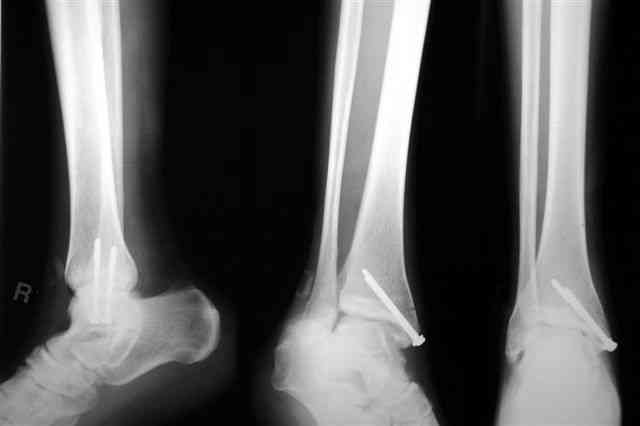

Бедро фиксировал длинной DCS.

По типу бриджинг плэйтин, крюком удалось низвести малый вертел и фиксировать винтом для восстановления медиальной стенки.

Снимки бедра и голеностопа еще не сфотографировал, обязательно представлю на форум

В приложении отправляю послеопер. снимки бедра и лодыжки обсуждаемого вчера больного.